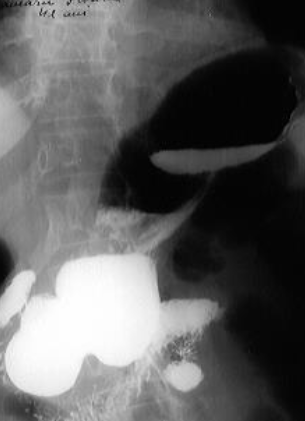

Hernie hiatală

Hernie hiatală prin alunecare

Hernie hiatală prin rostogolire

Hernie hiatală - brahiesofag